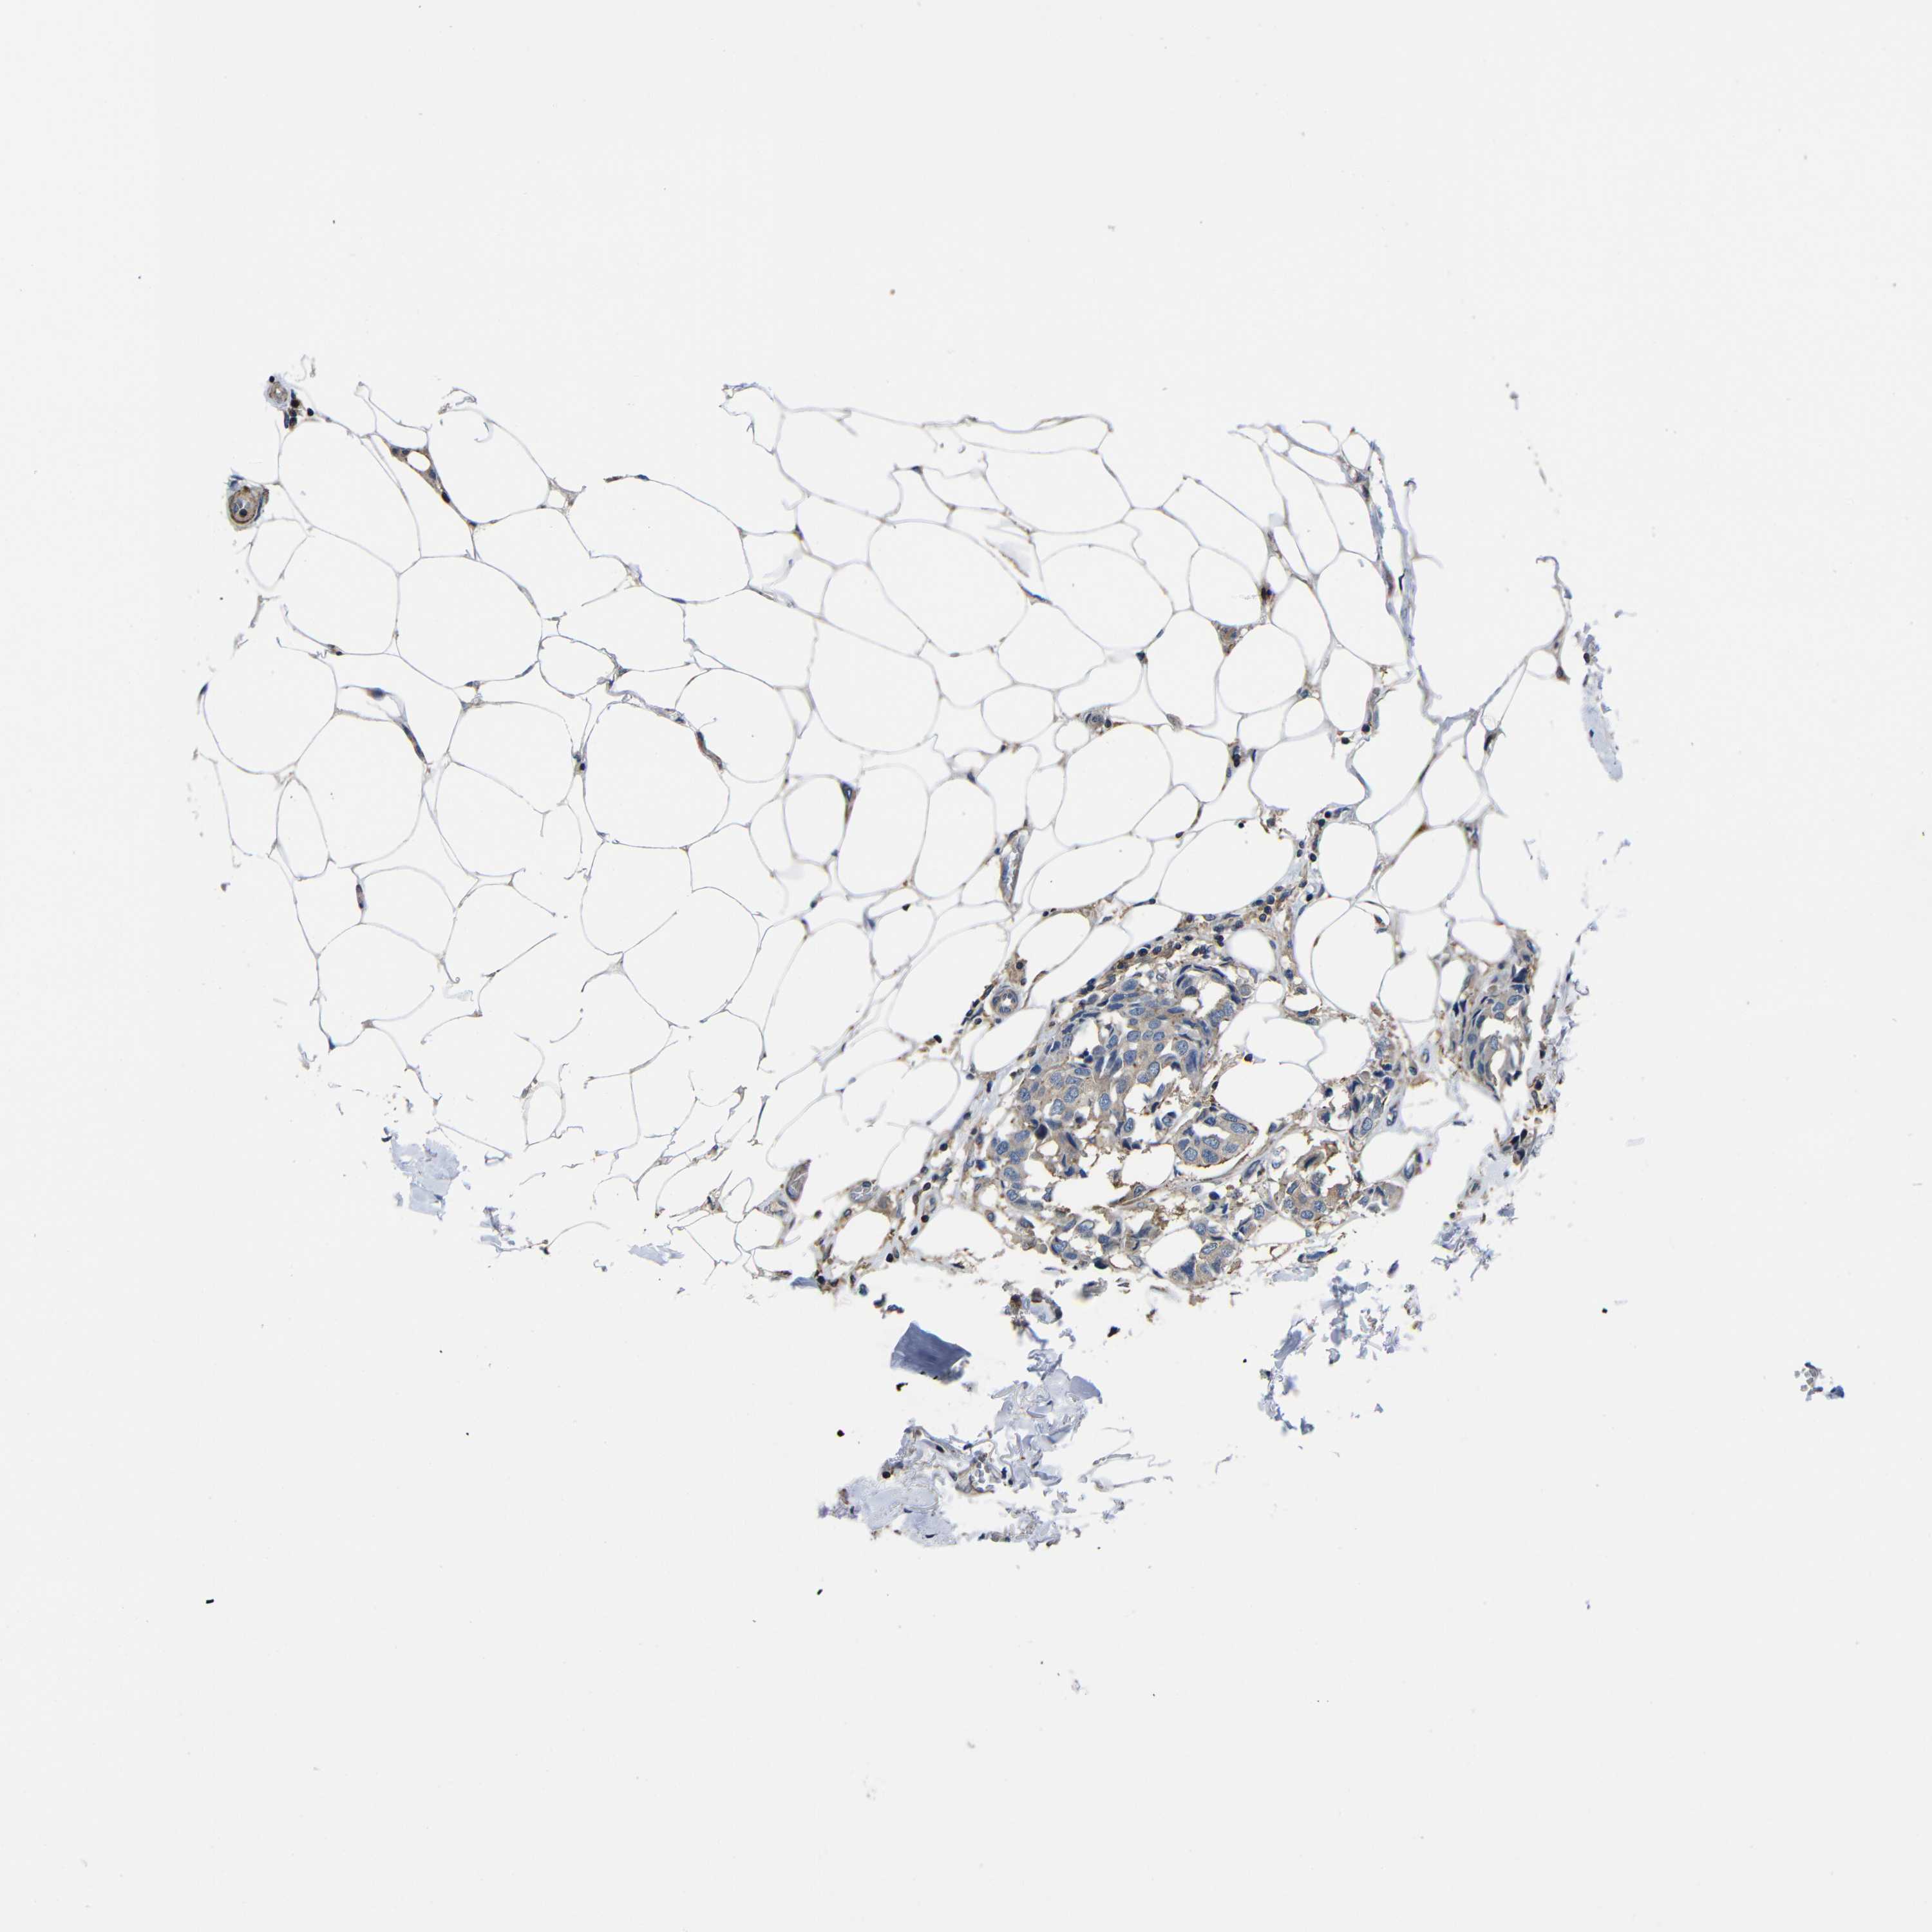

BRCA TCGA BRCA VALIDATION PROTEIN EXPRESSION

Breast cancer

Human cancer

Breast invasive carcinoma